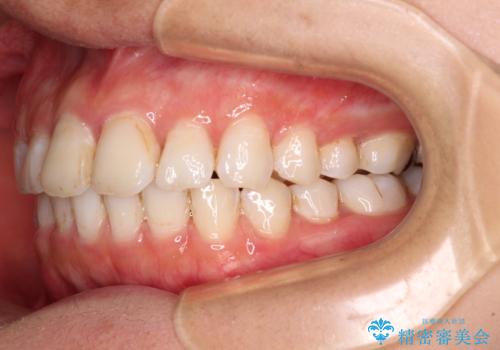

前歯の捻れを改善 インビザラインによる矯正治療

- 前歯の翼状捻転を気にして来院された患者様です。

全体的に叢生は軽度であったため、インビザラインにて矯正治療を行うこととしました。

前歯の幅の大きさも気になっていたため、IPRにより叢生を解消するとともに、歯の大きさも改善しました。